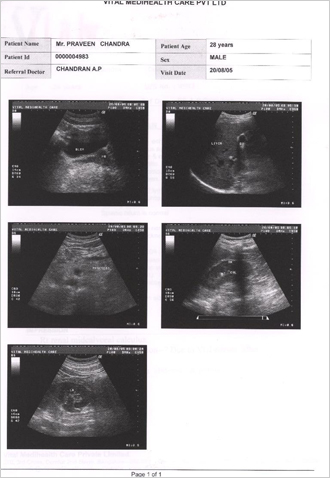

Condition of patient in beginning of Homoeopathic treatment for Kidney Calculus